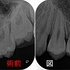

レントゲン

第二大臼歯に直接覆髄がしてありますが、根の方には大きな透過像(骨が溶けている場所)

第一大臼歯遠心根にもうっすら透過像あり。

今回のケースは珍しくフィステル(膿の出口)が2か所あります。

ということは膿の原因場所が2か所あると推測されます。

第一大臼歯はそんなに問題無いように見えるので、とりあえず第二大臼歯の治療を行うことにしました。